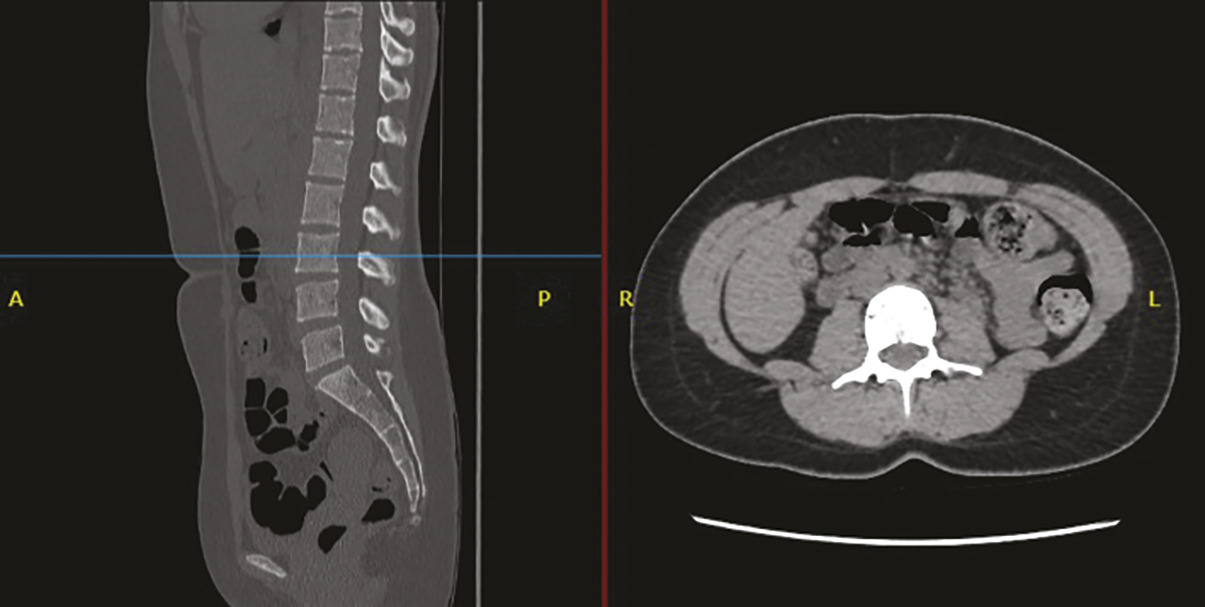

Pour déterminer la surface musculaire en imagerie scanner, deux étapes sont nécessaires.

La première consiste à identifier la troisième vertèbre lombaire puis à choisir une coupe passant par celle-ci (fig. 1).

Sur cette coupe, les muscles sont ensuite identifiés à la fois grâce à leur densité et à leur localisation anatomique, ce qui permet de déterminer la surface musculaire (fig. 2). Comme pour l’indice de masse corporelle, il est recommandé de rapporter la surface musculaire à la taille au carré pour obtenir l’indice de surface musculaire (ISM).